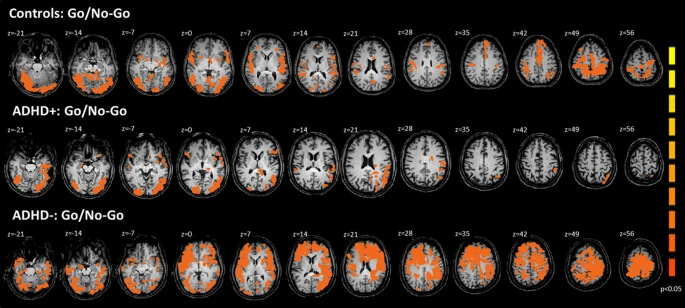

Below is a scan that shows the difference between an ADHD and a non-ADHD brain during a group experiment. The participants went through an attention task called “go/no go.” The ADHD group showed diminished activation, while the non-ADHD group showed “increased activation in the following anatomical regions: bilateral on inferior frontal gyrus, insula, postcentral gyrus, putamen, caudate, thalamus, anterior cingulate cortex, precuneus, globus ballidus and inferior temporal gyrus.” Read the full study here. The activity in brain circuits is clearly visible and trackable.